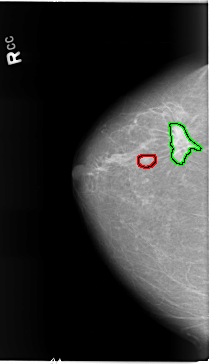

RIGHT_CC LINES 5824 PIXELS_PER_LINE 3360 BITS_PER_PIXEL 12 RESOLUTION 50 OVERLAY

FILE: B_3090_1.RIGHT_MLO.OVERLAY

TOTAL_ABNORMALITIES 2

ABNORMALITY 1

LESION_TYPE MASS SHAPE OVAL MARGINS CIRCUMSCRIBED

ASSESSMENT 3

SUBTLETY 3

PATHOLOGY UNPROVEN

TOTAL_OUTLINES 1

ABNORMALITY 2

LESION_TYPE MASS SHAPE IRREGULAR-ARCHITECTURAL_DISTORTION MARGINS SPICULATED

ASSESSMENT 5

SUBTLETY 5

PATHOLOGY MALIGNANT

FILE: B_3090_1.RIGHT_CC.OVERLAY